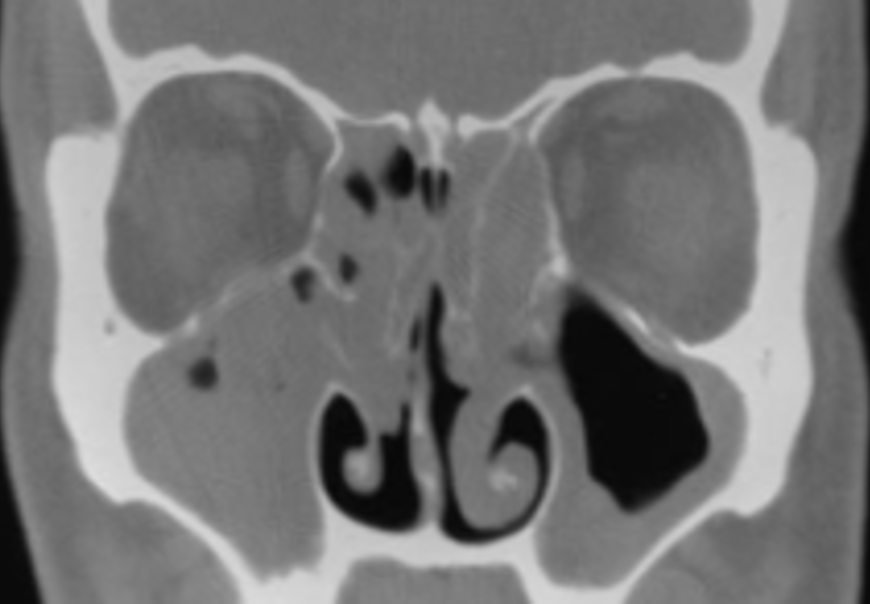

아침 운동을 마치고나서 샤워를 하는데 엉켜있는 코피가 보인다. 출근 대신에 이비인후과 진료를 선택하여 병원을 찾았더니, 만성 부비동염과 함께 비밸브재건을 해야 한다며 입원을 권유한다. 비밸브는 코 내부 가장 좁은 부위로 코 안의 기류가 천천히 흐르도록 조절하여 가습, 여과, 후각 작용 등이 충분히 이루어 질 수 있도록 기능하는 곳인데 전자 내시경 및 3D-CT 등을 통해 확인하니 이곳 연골이 망가졌단다. 또 축농증이라 일컫는 부비동염이 있어 코가 막혀서 피멍이 들어있다며 함께 수술해야 한단다.

70세 이후에는 수술을 받기위해 전신마취가 필요하며, 전신마취를 위해서는 순환기내과와 호흡기내과등의 협진이 필수라며 건강검진을 먼저 하란다. 입원을 위하여 세시간의 신체검사를 모두 받은 후, 부비동염과 비밸브재건을 위한 3박4일의 입원실로 들어왔다.